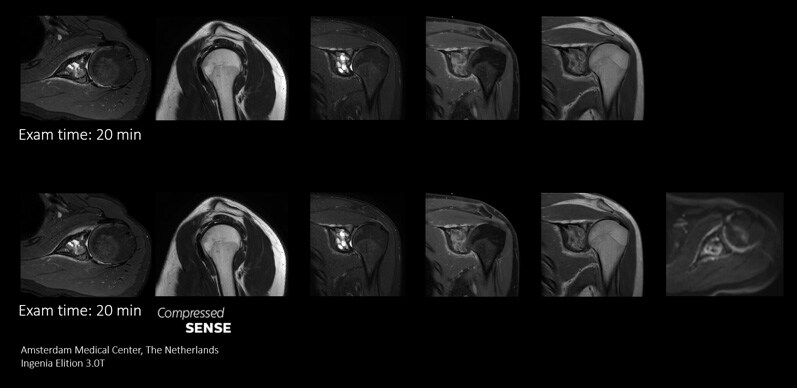

Philips’ Compressed SENSE is very easy to use. Only three parameters are required to use Compressed SENSE.